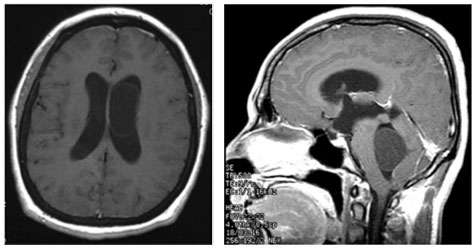

- When cysticercosis affects the brain or spinal cord, the condition is called neurocysticercosis. Usually, the cyst causes inflammation in the brain tissue itself which results in a seizure. In about 10% of neurocysticercosis cases, the cysts are found within the cerebral ventricles or in the cerebrospinal fluid spaces (cisterns). This can cause hydrocephalus or symptoms due to pressure on the brain.

- In about 10 percent of neurocysticercosis cases the cysts are found within the cerebral ventricles or in the cerebrospinal fluid spaces (cisterns). This can cause hydrocephalus or symptoms due to pressure on the brain.

- The most common symptoms are related to hydrocephalus. The onset of symptoms, including headache, vomiting, seizures, can be rather sudden and can result in death. A degenerating cyst can cause symptoms of meningitis.

- Diagnosis is best made by magnetic response imaging (MRI), although intraventricular cysts can sometimes be very difficult to detect on routine MRI imaging.